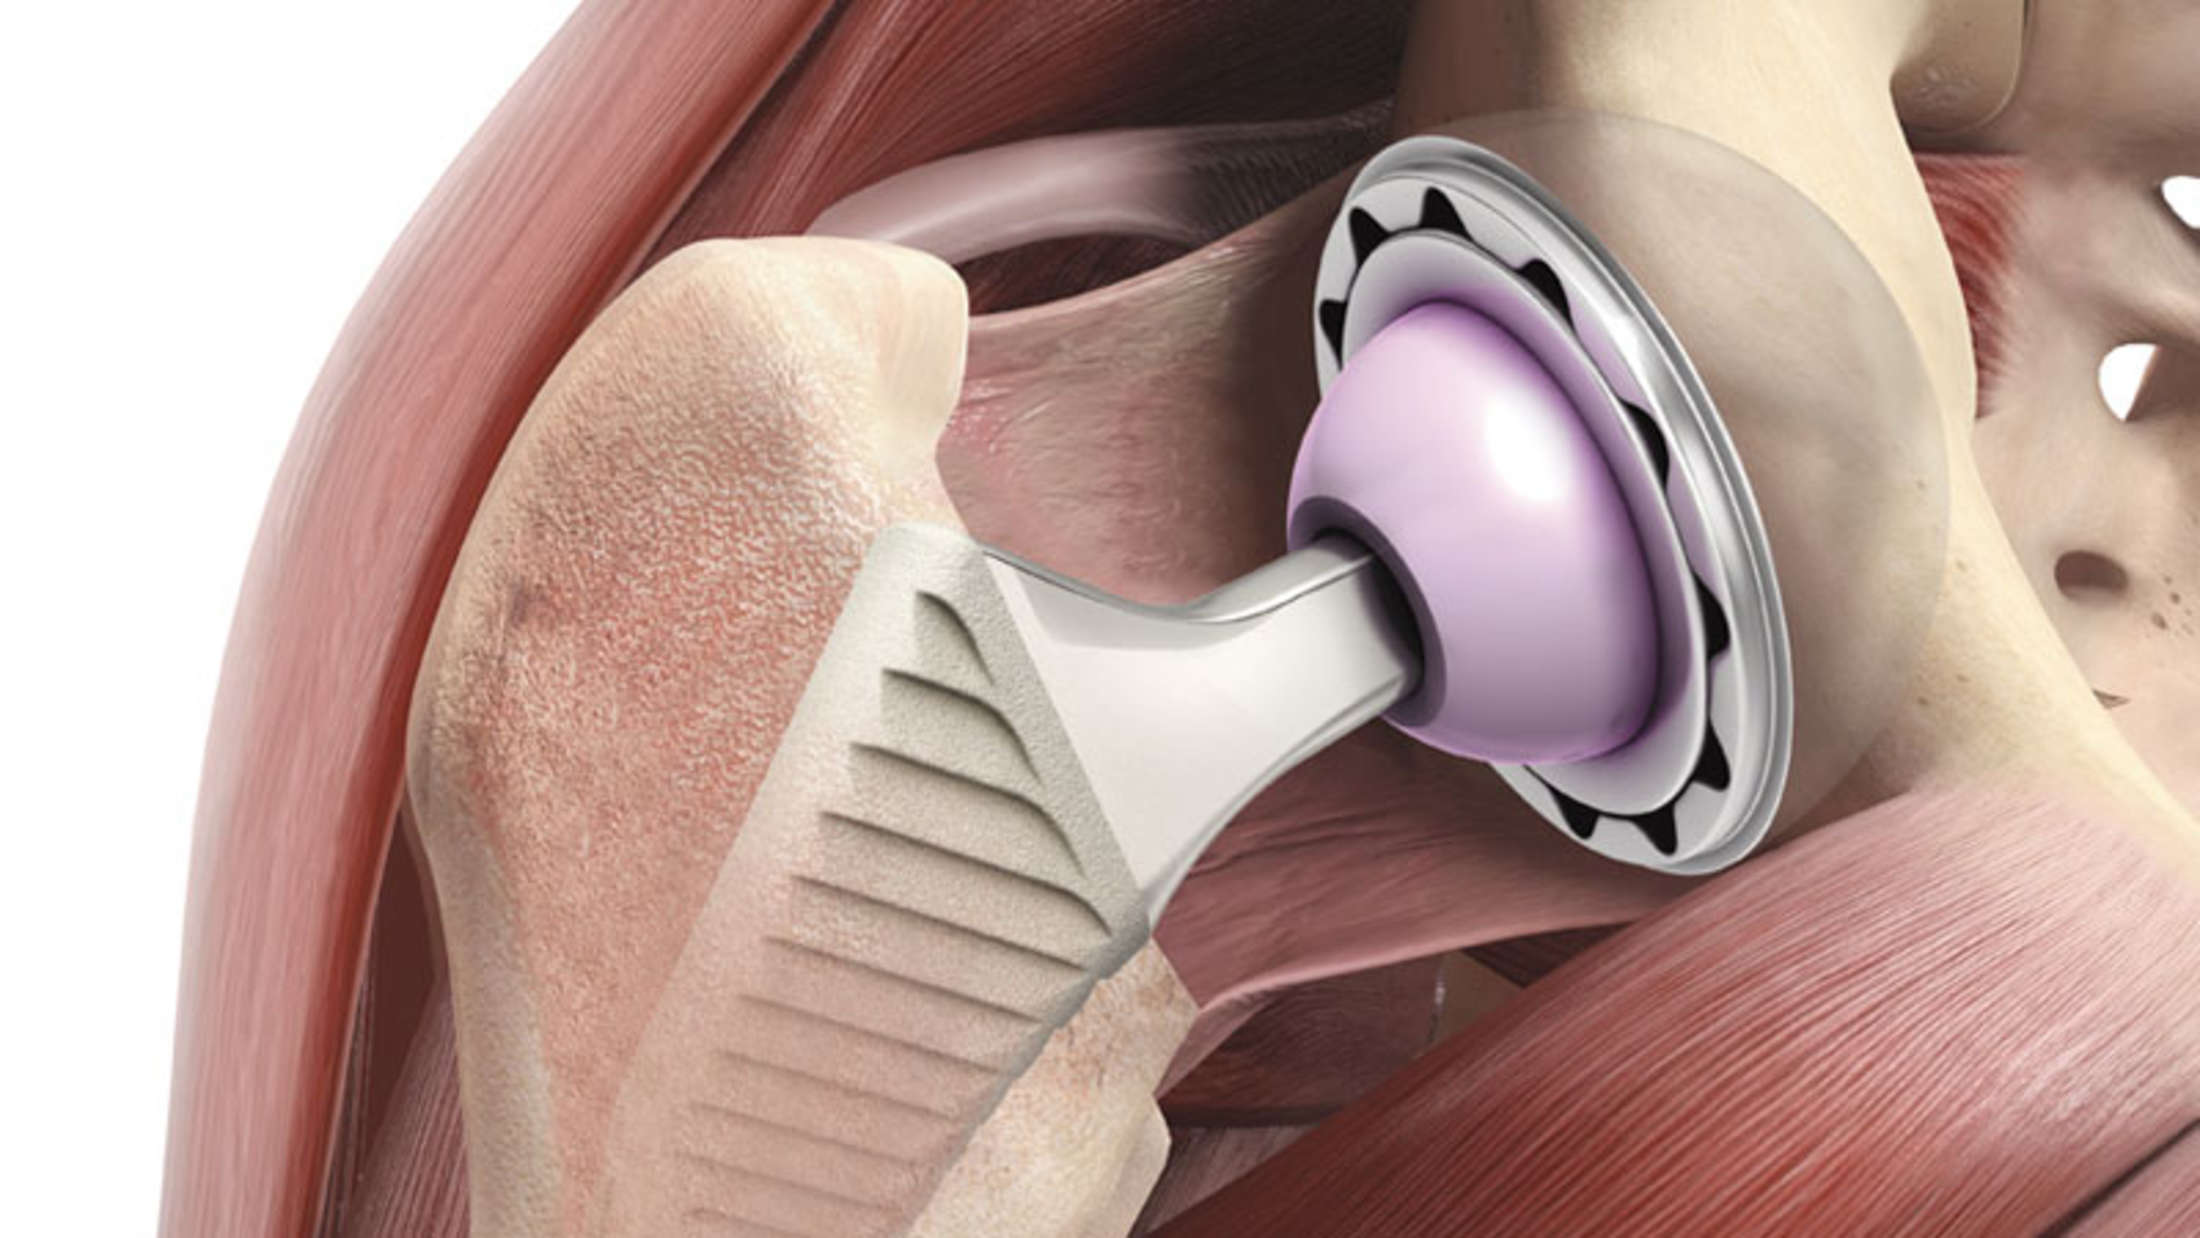

Эндопротезирование тазобедренного сустава: фото и схемы